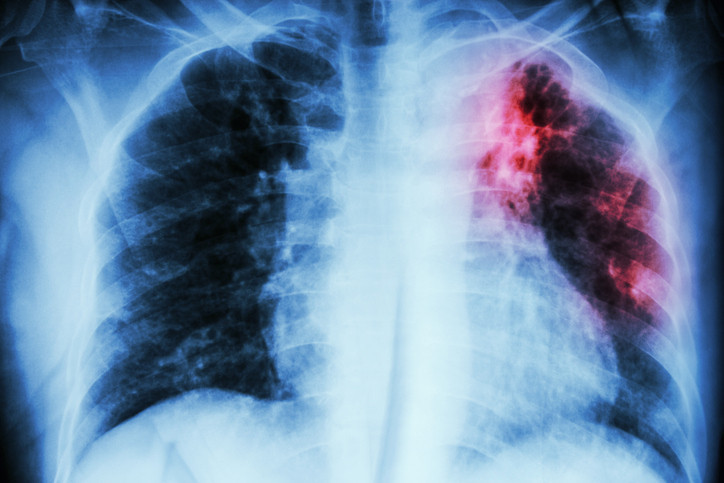

Vücut burada çoğalan mikropları yok etmek için iltihap karşıtı hücrelerini bölgeye gönderiyor. Bu savaş sırasında alveoller, yani akciğer dokuları sıvı iltihap hücreleri ve bakterilerle dolmaktadır. Bunun sonucunda, vücutta oksijen seviyesi düşerken; ateş, öksürük ve göğüs ağrısı gibi sorunlar başlamaktadır.